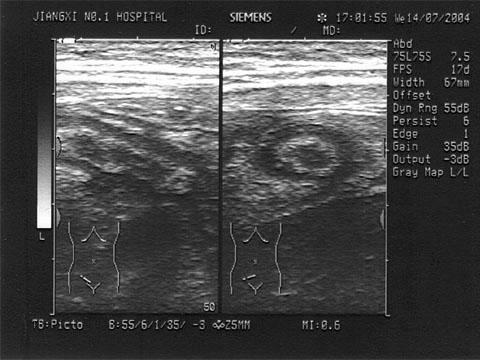

问题 女,54岁。反复便秘,腹泻就诊。PE:左中腹可扪及一肿块,质硬,结节状,OB(Ⅱ),结合超声声像图,诊断为?(?)

选项 A.左肾 B.结肠癌 C.肠系膜淋巴结 D.腹膜后肿块 E.肠结核

答案 B